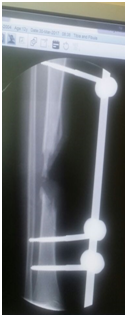

Three month later, the external fixator was removed; back slab was applied for 10 day to decrease the possibility of pin site infection. Final augmentation of the grafting was done by fibular allograft and fixed by 12 whole LCP. The nerve grafting performed (Figures 5a-5c). Two months later, the patient was seen in the clinic, he was able to move his ankle, radiography of the tibia demonstrated a remarkable filling of the gap by bone (Figures 6a-6d).

• Figure 6a-c Postoperative follow up 2 months later.